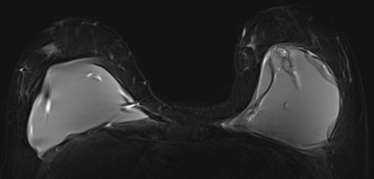

Female with BRCA1 mutation underwent breast cancer screening

Figure 1. 33-year-old female with BRCA1 mutation underwent breast cancer screening with breast MRI, which demonstrated heterogeneously dense breast tissue with mild parenchymal enhancement and no suspicious enhancing lesions (normal breast MRI). The typical MRI protocol for screening is based on T1-weighted imaging followed by intravenous gadolinium contrast to assess for enhancing breast lesions. T2-weighted imaging and diffusion weighted imaging can be used to improve lesion characterization. Our institution’s protocol includes (A) T2-weighted short tau inversion recovery (STIR), (B) T1-weighted without (C) and with fat saturation imaging, and (D) dynamic T1-weighted post contrast imaging taken 90 seconds apart for a total of four phases (only the first phase is shown here). Reformats including (E) maximal intensity projection (MIP) with angiogenesis mapping and (F) subtraction are performed.